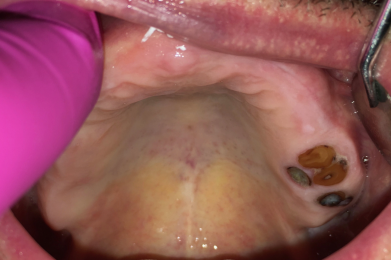

- Prothesen und Schleimhäute zeigen weißliche Beläge bzw. Haftcreme-Reste

- Prothesen lösen sich immer wieder unkontrolliert beim Sprechen, häufiger fallen die Prothesen einfach aus dem Mund / Sprache ist undeutlich und Person spricht auffällig wenig

- Essen wird verweigert / Teilprothesen bzw. Totalprothesen vorhanden